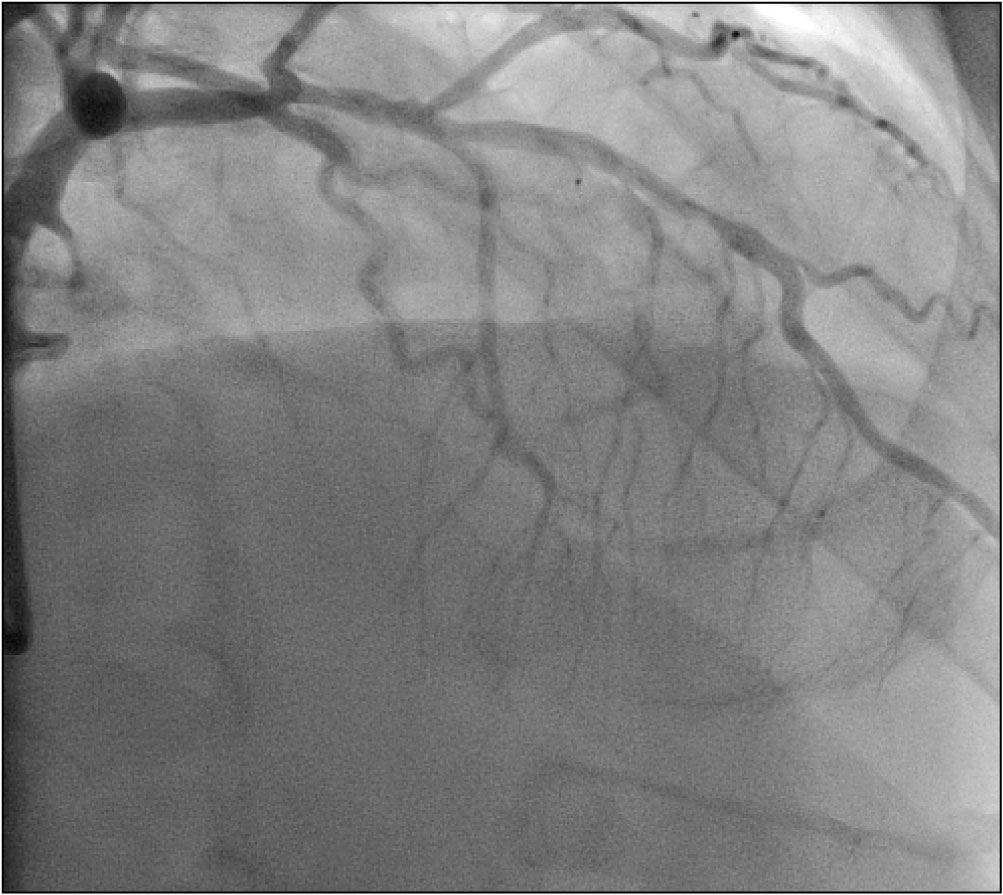

Sedmašedesátiletý muž byl v listopadu roku 2017 vyšetřen v katetrizační laboratoři Pracoviště invazivní a intervenční kardiologie Interní kardiologické kliniky FN Brno pro tři měsíce trvající progresi námahové dušnosti do funkční třídy NYHA III, nový záchyt fibrilace síní, přechodných depresí úseku ST v inferiorních svodech a echokardiografický nález systolické dysfunkce levé komory s globální hypokontraktilitou akcentovanou v oblasti baze dolní stěny a s celkovou ejekční frakcí levé komory 40 %. Koronarografie odhalila významnou stenózu ramus interventricularis anterior (RIA) levé věnčité tepny s angiografickou redukcí lumen přibližně 70 % a chronický uzávěr pravé věnčité tepny (arteria coronaria dextra, ACD) s dobře patrným kolaterálním zásobením z levé věnčité tepny (obr. 1–3 a video 1–3).

Rozsah koronárního postižení odpovídal střednímu rozsahu s hodnotou SYNTAX skóre II 20 bodů. Pacient byl dlouhodobě léčen jen pro hypertenzi a má nadváhu (body mass index 29,7 kg/m2), jinak je bez významných rizikových faktorů aterosklerózy. Postižení obou tepen bylo hodnoceno jako vhodné ke katetrizačnímu ošetření a po diskusi s pacientem byla na leden 2018 naplánována elektivní koronární intervence (PCI). Plánovanému zákroku předcházelo zahájení podávání duální antiagregace (kyselina acetylsalicylová v dávce 100 mg denně a clopidogrel 75 mg denně). Výkon byl proveden za použití dvou arteriálních přístupů. Do ústí pravé věnčité tepny byl zaveden katétr Vista JR4 7F (Cordis – Cardinal Health, USA) cestou pravého femorálního přístupu, do ústí levé věnčité tepny pak zaváděcí katétr Vista XB4 6F (Cordis – Cardinal Health, USA) pravým radiálním přístupem (obr. 4 a video 4).

Za podpory mikrokatétru Finecross a pomocí vodičů Fielder XT a Gaia Second (Asahi Intecc, Japonsko) byl proveden pokus o prográdní rekanalizaci standardní cestou (tzv. wire escalation technika), vodič Gaia Second prochází podél chronického uzávěru jen do disekce bez možnosti sondáže pravého lumen distálně od uzávěru (obr. 5 a video 5).